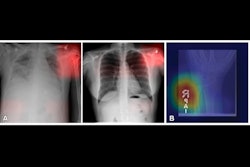

Bias and data transparency have been two focal points for radiologists using AI. AI advocates say that for the technology to further advance into the clinic, these issues among others need to be addressed. They also say that current datasets do not adequately represent diverse populations. People who are in minority groups are likely to be under-represented in datasets, so they may be disproportionately affected by AI bias.